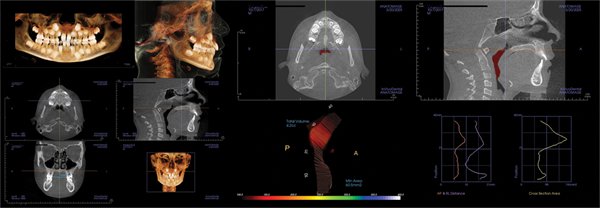

Patient one: Refer to ENT (Figs. 1–3)

The first patient was an almost 9-year-old girl referred for crowding. Her history included mouth-breathing, snoring, and an inability to breathe effectively through her nose. After discussion of airway concerns, it was noted a previous ENT physician had told the family there was no need for intervention.

Facial evaluation revealed an angular facial pattern with a retrusive mandible. The smile bones were tipped inward, accentuating the Curve of Wilson, and the buccal corridors were dark. The panoramic X-ray showed crowding primarily in the anterior. The second molars appeared to have adequate room to erupt. The lateral cephalometric view showed a Class II tendency and an open bite. The airway view on CBCT demonstrated an adequate MCA, but poor tongue posture and enlarged adenoids were noted. The palatal width was 28 mm, well under the 31 mm suggested by McNamara.

The family was given a second referral to an ENT surgeon, who removed the tonsils and adenoids. Phase I treatment was initiated to include maxillary expansion and alignment of the mixed dentition. Progress X-rays demonstrated space for erupting teeth and a Class II malocclusion. The CBCT showed reduced adenoid size following surgery and a stable MCA of 108 mm. The palatal width increased to nearly 35 mm.

Following tonsillectomy and adenoidectomy, the patient’s parent reported resolution of snoring and bruxism, improved sleep quality, and noticeable improvement in daytime appearance.